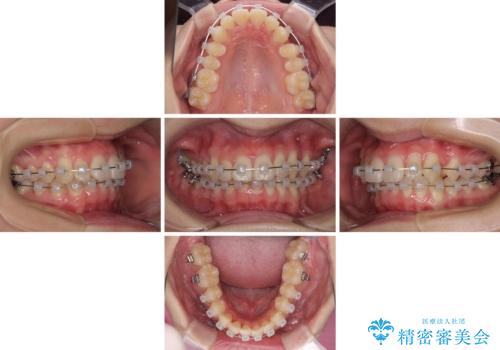

- 治療期間

- 1年6ヶ月

クロスバイト改善中には歯髄壊死を起こすリスクがあるため、神経に問題がないか確認しながら治療を進めて行く必要があります。

思っていたよりも早くクロスバイトは改善され、歯髄壊死に至ることなく、無事に治療を終えることができました。